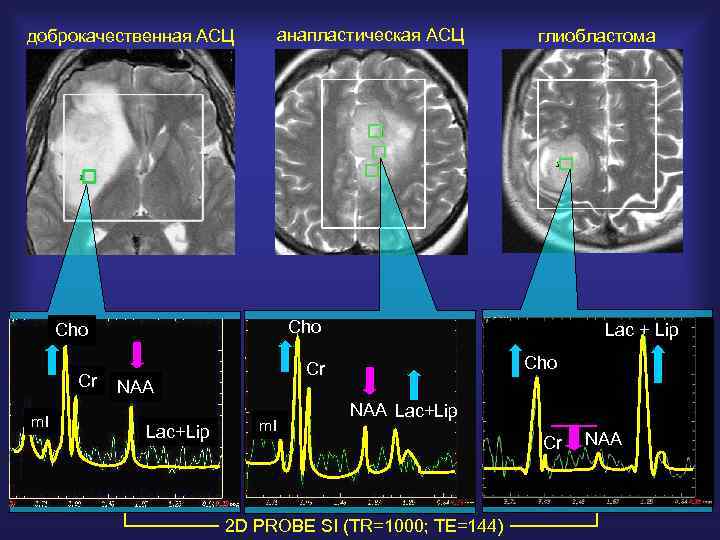

доброкачественная АСЦ анапластическая АСЦ Cho Cr m. I глиобластома Cho Cr NAA Lac+Lip Lac + Lip m. I NAA Lac+Lip 2 D PROBE SI (TR=1000; TE=144) Cr NAA